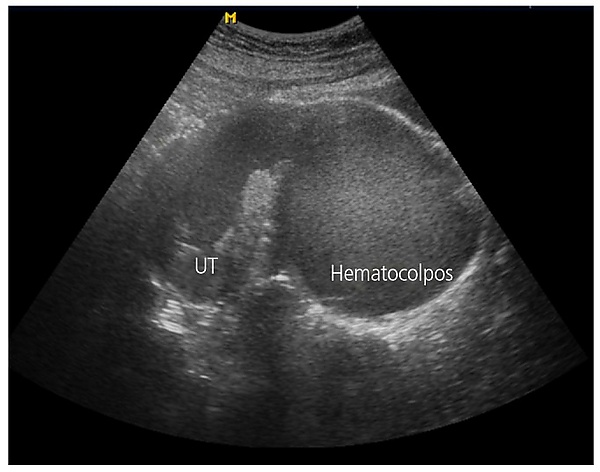

- Ультразвуковое исследование органов малого таза — при атрезии гимена визуализируется резко расширенное, заполненное жидкостью влагалище в виде эхонегативного образования, матка нормальных размеров расположена на верхнем полюсе гематокольпоса. Для аплазии нижней трети влагалища характерен двойной контур в зоне соприкосновения неперфорированного гимена с замкнутым влагалищем: овальное тонкостенное образование в дистальной части (гематокольпос) и шаровидное толстостенное образование (гематометра), содержимое которых может быть анэхогенным или неоднородным. Могут визуализироваться расширенные маточные трубы с анэхогенным компонентом (гематосальпинксы). При удвоении матки и влагалища с частичной аплазией одного из влагалищ определяются две матки, гематокольпос, неизменённые яичники и гематосальпинкс на стороне гематокольпоса[7].